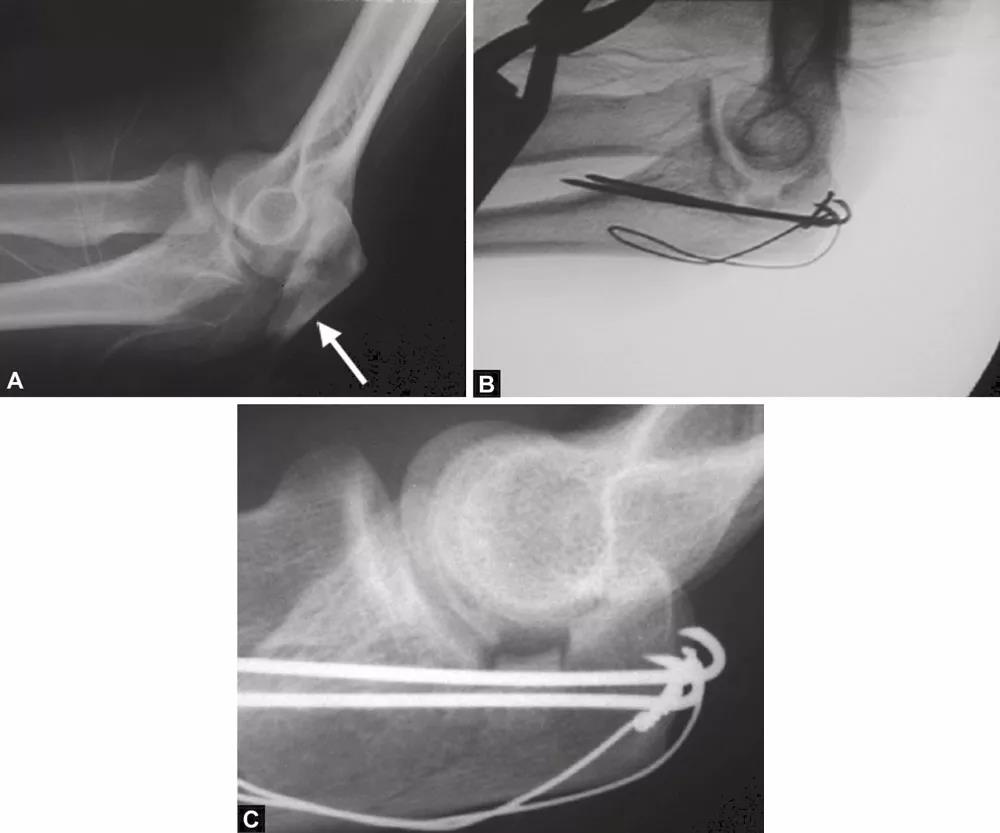

图3A~C关节压缩骨折在鹰嘴斜位片中完全隐匿。在箭头的部位变窄可能是一个提示。如果不知道这种可能性,医生就会忽略该手术X线片检查中明显的关节面压缩骨折。术后标准的侧位片良好地显示了关节面压缩骨折。该医生未能完成最初的手术目标